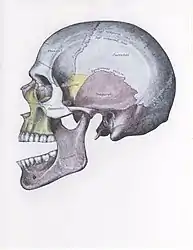

- Side view of the skull with anterior dislocation of jaw.

There are four different positions of jaw dislocation: posterior, anterior, superior and lateral. The most common position is anterior, while the other types are rare. Anterior dislocation shifts the lower jaw forward if the mouth excessively opens. This type of dislocation may happen bilaterally or unilaterally after yawning. The muscles that are affected during anterior jaw dislocation are the masseter and temporalis which pull up on the mandible and the lateral pterygoid which relaxes the mandibular condyle. The condyle can get locked in front of the articular eminence. Posterior dislocation is possible for people who get injured by being punched in the chin. This dislocation will push the jaw back affecting the alignment of the mandibular condyle and mastoid. The external auditory canal may be fractured. Superior dislocations occur after being punched below the mandibular ramus as the mouth remains half-open. Since great force occurs in a punch, the angle of the jaw will be forced upward moving towards the condylar head. This can result in a fracture of the glenoid fossa and displacement of the condyle into the middle cranial fossa, potentially injuring the facial and vestibulocochlear nerves and the temporal lobe. Lateral dislocations move the mandibular condyle away from the skull and are likely to happen together with jaw fractures.[4][5]

The joint involved with jaw dislocation is the temporomandibular joint (TMJ). This joint is located where the mandibular condyles and the temporal bone meet.[4][6] Membranes that surround the bones help during the hinging and gliding of jaw movement. For the mouth to close it requires the following muscles: the masseter, temporalis, and medial pterygoid muscle. For the jaw to open it requires the lateral pterygoid muscle.[4]